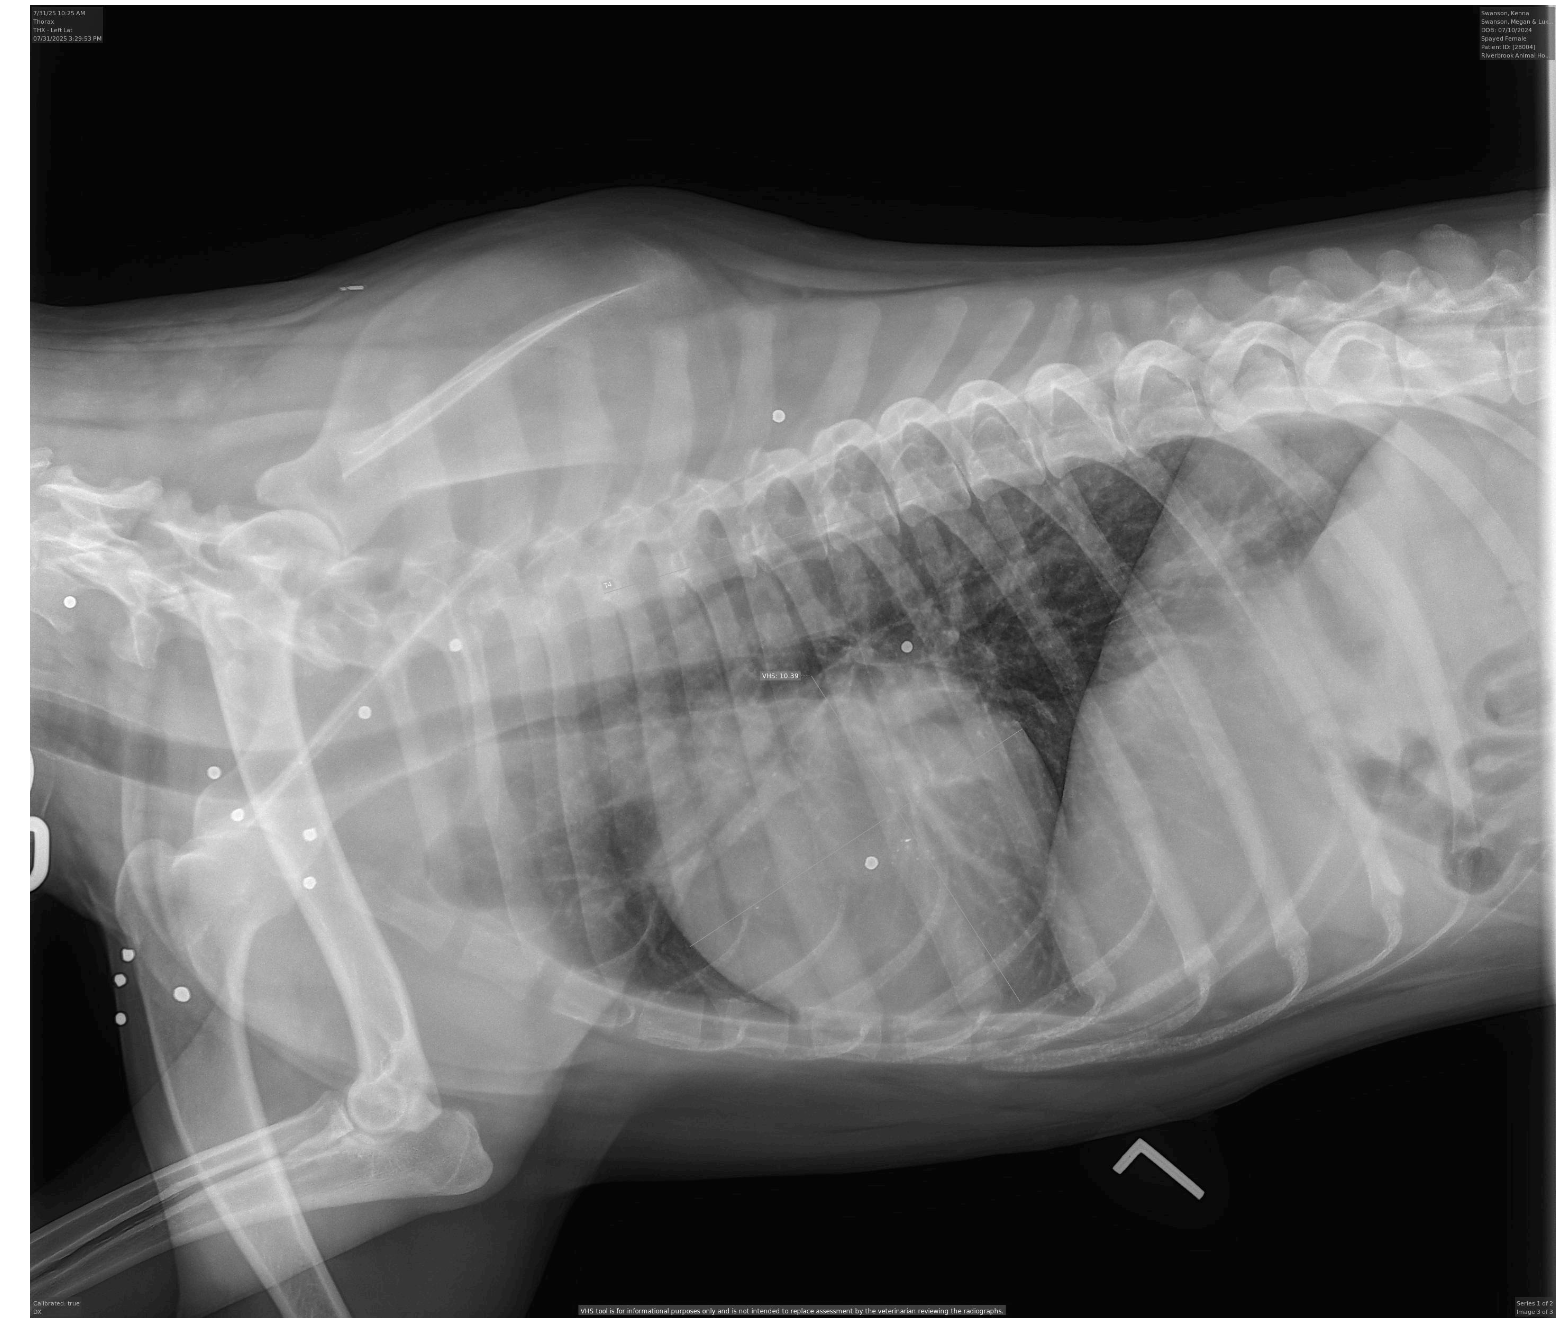

After being treated for heartworms and for Ehrlichia at the beginning of May, Kenna felt a bit better…but still not 100%. She was taken back into the vet for some bloodwork. The results have us confused, and concerned. Kenna’s white blood cell count was over 50,000, an excessive amount for a number that should be closer to 15,000. Combined with other abnormalities on bloodwork, the doctors believed Kenna is battling some type of infection- but of what we don’t know. Additionally, radiographs revealed that Kenna’s body is riddled with BB gun bullets. We’re devastated to think of all she went through before coming to us.